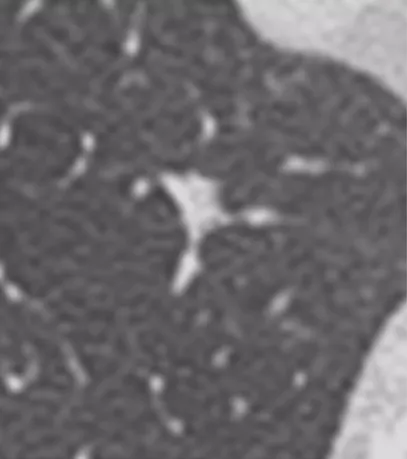

内部特征:燕麦圈征(开放支气管征)

还有非常容易被大家忽略的一个特点(如上图所示),文献上把这个病灶称为燕麦圈征,这不是个好征象。由开放气道周围的肿瘤细胞或非肿瘤细胞增生所致,多见于肺腺癌和肺朗格汉斯细胞组织细胞增多症。尤其是女性病人出现这种征象的概率比较高,出现之后一定要手术。